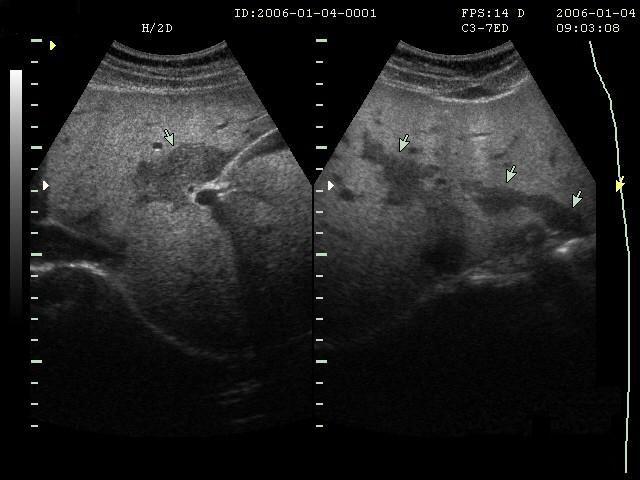

慢性肝病复查,常常要做腹部彩超、CT、核磁共振,如果患者少量吃东西,一般来说影响不是很大。但如果患者吃的过饱,可能有很大的影响。

1.吃得过饱,胃肠道的体积会增大,可能不同程度的遮挡周围的脏器,特别是会导致不容易看清楚肝脏的边缘,甚至掩盖某些细节。

2.胃肠的内容物,会阻挡彩超超声波的穿透,使其后方的器官显示差,或者部分不显示。

3.彩超观察胆囊和胆道系统也是重要的,检查前吃东西,特别是油腻的东西后,胆囊会发生收缩,导致检查的图像不够清晰。